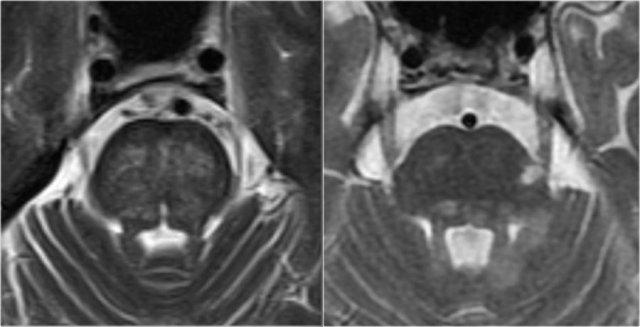

Tổn thương thân não đối xứng trong bệnh lý mạch máu nhỏ (trái) so với tổn thương MS không đối xứng điển hình (phải)

Tổn thương thân não

Trong MS, các tổn thương thân não thường có vị trí ngoại vi.

Trong bệnh lý mạch máu nhỏ, thân não có thể bị tổn thương, nhưng thường có tính chất đối xứng và nằm ở vị trí trung tâm.

Hình bên trái là ảnh cắt ngang chuỗi xung T2W minh họa tổn thương thân não do mạch máu điển hình, với tổn thương trung tâm của các sợi cầu não ngang.

Hình bên phải là ảnh cắt ngang chuỗi xung T2W của thân não bệnh nhân MS, cho thấy các tổn thương chất trắng điển hình nằm ở ngoại vi, thường ở hoặc gần bó sinh ba, hoặc tiếp giáp với não thất IV.